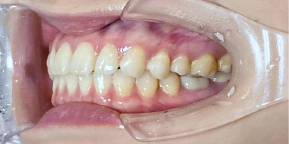

33歳女性のビフォーアフター

| 診断 | 空隙 |

| 治療方針 | 治療方針:前歯の咬合関係改善と空隙閉鎖を主な目的にて主にIPR(歯と歯の間をわずかに削合してスペースを獲得する方法)を組み込んだ動的矯正治療を行い、空隙、前歯咬合を改善後、保定を行う。臼歯部の咬合関係はプランの都合上維持することとした。 |

| 治療費 ※ | 67万8千円(診断、型取り、矯正中のメンテナンス、保定装置を含む料金) |

| 治療期間 | 6か月 |

| リスク | 1日20時間以上マウスピースを使用できない場合、歯が動かなかったり、想定しない誤差により不完全に終わる可能性がある。装着時や食事時に痛みを伴う。歯肉退縮や虫歯になるおそれがある。また、指導通りに装着できていない場合や適切なブラッシングが出来ていないとそのリスクが高くなる。歯根が短くなることがある。ごくまれに歯の神経が損傷してしまうことがある。過去にぶつけたり深い虫歯治療をしたことがあるとそのリスクはやや高くなる。矯正後には保定装置が必要。適切な使用ができない場合、後戻りの原因となる。将来的に歯並びが動いて再矯正が必要な場合がある。親知らずが正常に生えていない場合、その可能性がやや高くなる。 |